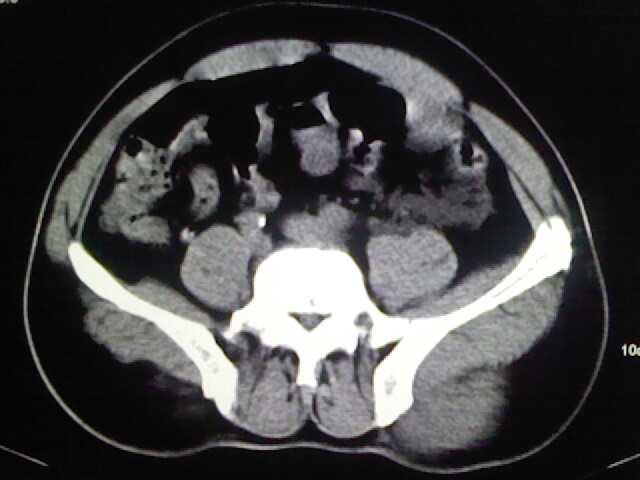

以下是引用zsl6918在2009-2-7 7:29:00的发言:[br]请提供介入的方式方法,肾及输尿管改变考虑与介入损伤有关,漏了,尿液外渗。

以下是引用余辉在2009-2-7 8:27:00的发言:[br]可能是硬化剂烧穿囊壁进入肾盂输尿管了,尿漏。不除外介入或碎石术后合并感染[br]患者术后怀疑结石,接着就碎石了?就怀疑没有确诊吗?碎石用的什么方法?气压弹道还是体外超声?如果这样的话责任人都难找

以下是引用随光逐影在2009-2-7 8:46:00的发言:[br]支持3楼意见。[br]另:不排除左肾及肾周感染可能。